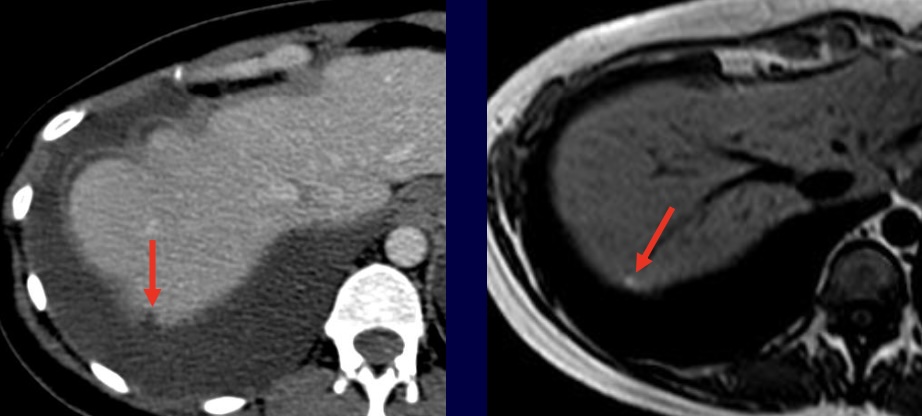

Endométriome (implant hémorragique si ≤ 1 cm, aspécifique si isolé)

- écho : fin piqueté échogène homogène, spots pariétaux hyper, ± septas, multiples++

- ± niveau liquide-liquide, caillot (déclive, mobile, avasculaire), hématosalpinx

- IRM : HT1 ≥ graisse, shading en T2 (HT2 20% voire hT2 si ancien)

- complications : décidualisation pdt grossesse, surinfection, transformation maligne

DD KLH : couronne hypervascularisée et HT1 < graisse

DD KLH : couronne hypervascularisée et HT1 < graisse